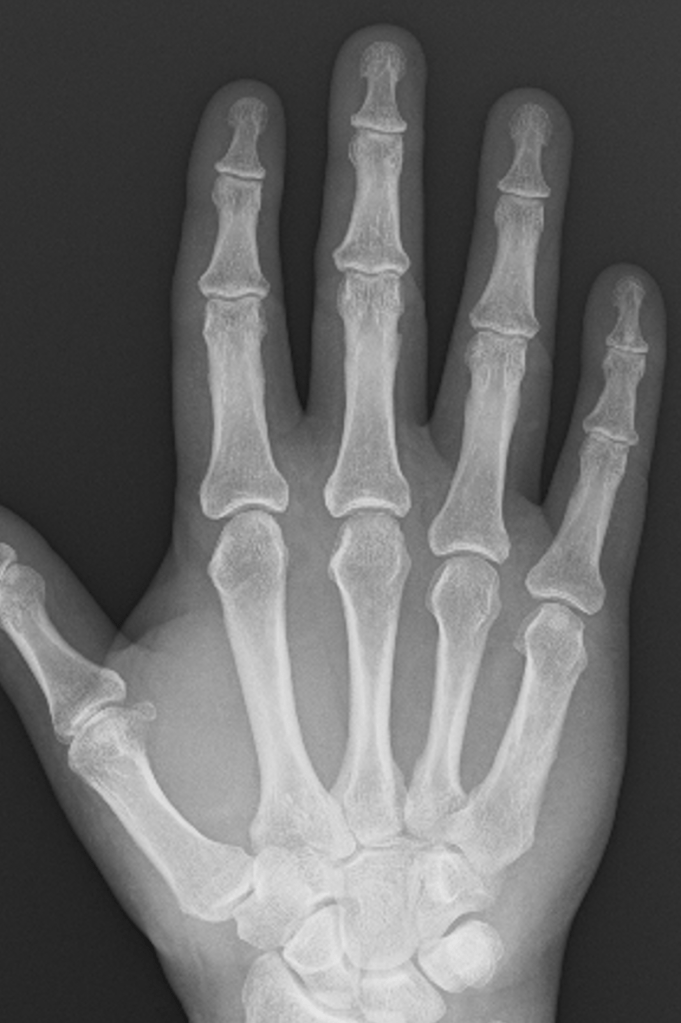

Loss of joint Space

In young patients, there are thick cartilage caps on the ends of the bones within the small joints of the hand. With age, these cartilage caps slowly wear from constant use, despite the body’s regenerative processes. A normal joint, therefore, has much less cartilage at 50 than at 20, and by the time people reach 80+ years, there is often very little cartilage left.

The GAP between the bones on an xray represents the space occupied by the cartilage, and it is very easy to predict how much cartilage is left in a joint simply by looking at the amount of space between the bones – the more space the more cartilage, and generally speaking the more healthy the joint.